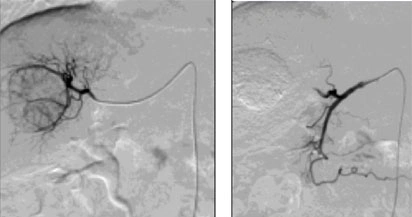

Sebbene si tratti di una forma rara, il carcinoma fibrolamellare viene trattato nella maggior parte dei casi come il carcinoma epatocellulare, con approcci terapeutici che possono includere chirurgia, trapianto di fegato, chemioembolizzazione o terapia sistemica.